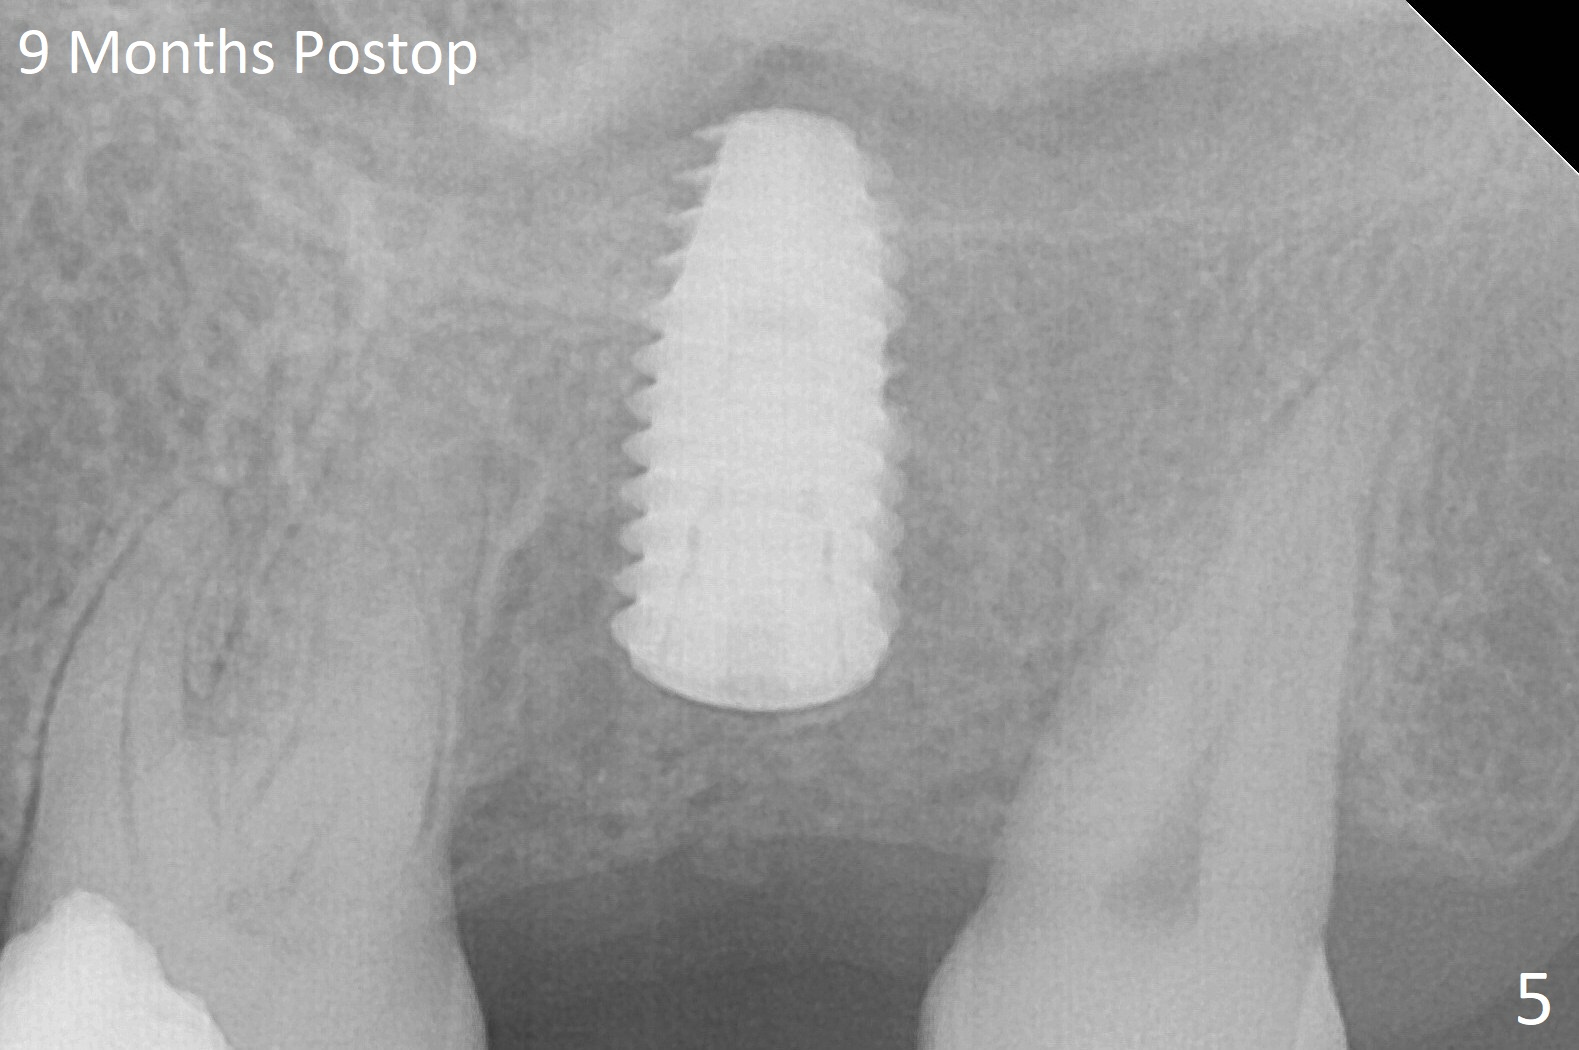

Bone forms overlying the implant plateau 9 months postop (Fig.5), which is confirmed in implant uncover.